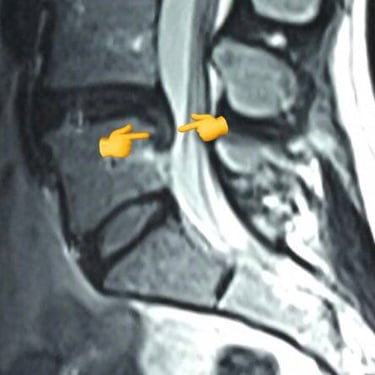

Symptoms: Severe disabling low back and sciatica pain for two years

An intriguing case involved severe herniation and disc rupture between L4 and L5 vertebrae, causing intense pain. Opting out of surgery, the patient chose to try Discogel. Due to severe foraminal stenosis from the extruded disc, the Discogel injection was cautiously prolonged to one hour. Post-injection CT scan revealed effective penetration into fragmented disc components in the narrowed foraminal space.

The patient's pain gradually diminished after 4-5 weeks, and complete relief was achieved after several months.

The first image is six months post-injection, and the second image is three years post-injection."